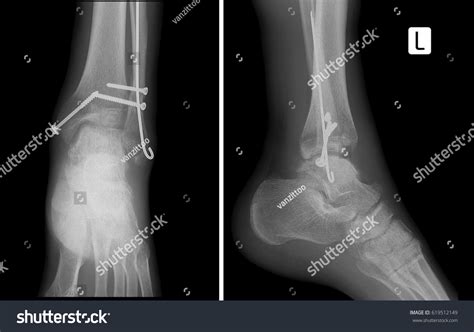

However, if the Xray indicates that the joint surface is uneven or that the bone is severely displaced, surgery may be recommended. This is often referred to as Open Reduction Internal Fixation (ORIF), where a surgeon uses hardware like metal plates and screws to hold the bones in the correct anatomical position while they heal. Following surgery, you will likely undergo follow-up Xrays periodically to monitor bone union.

Comminuted Fracture Bone is shattered into pieces. Surgery (ORIF).